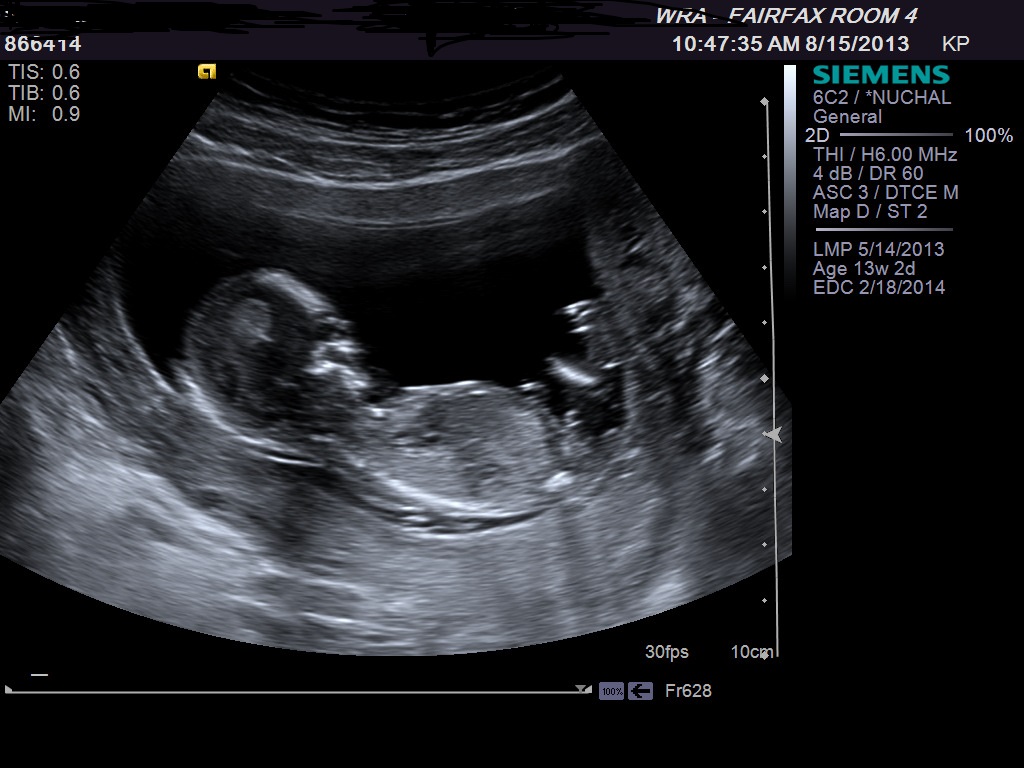

ultrasound 13 weeks is it boy or girl

Attachment 13978

When nub is easy to find